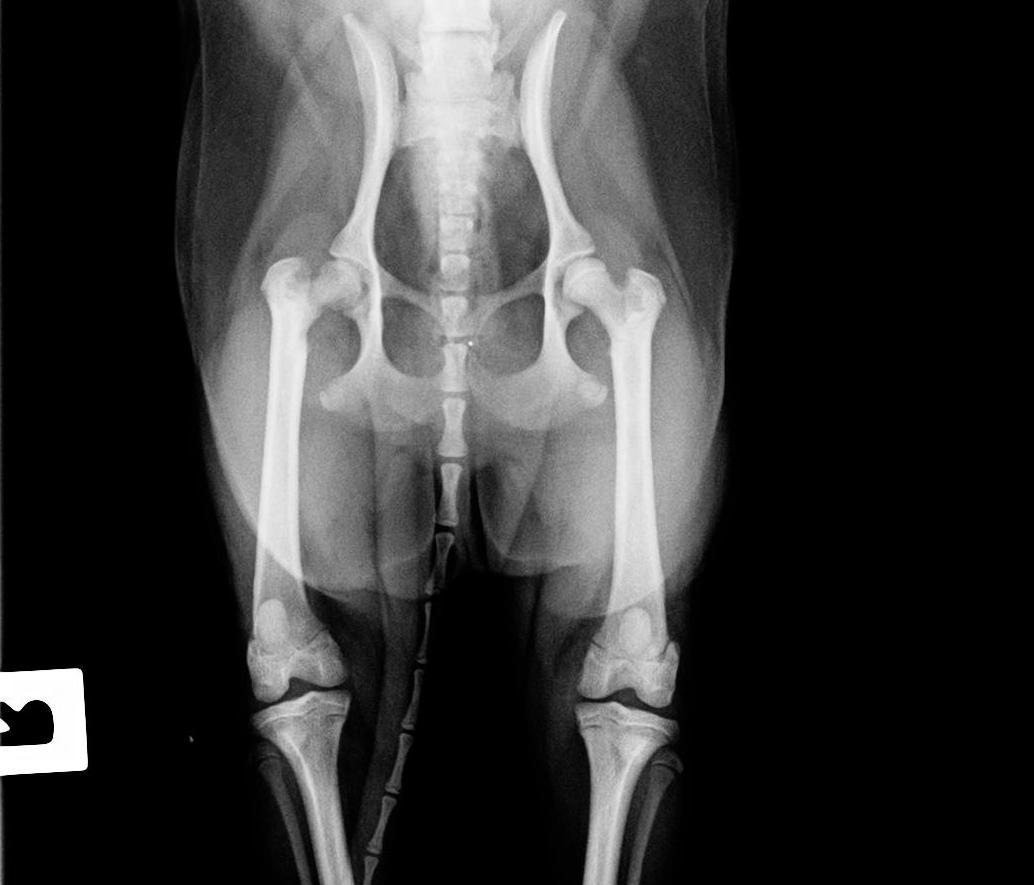

Диагноз ставится врачом-ортопедом, на основании клинической картины, данных анамнеза и рентгенографического исследования.

Болезнь Пертеса у собак следует отличать от других заболеваний со схожими внешними симптомами - вывихом коленной чашечки, дисплазии тазобедренного сустава.